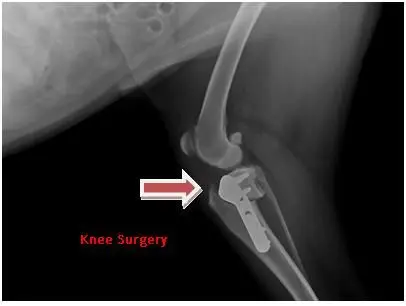

Radiographs help us in many ways.  They help diagnose broken bones, may show possible foreign bodies, bladder stones, masses, abnormalities of heart and lungs and so much more.  This can help pet owners see what is happening inside their animals and help them understand why certain treatment courses are then recommended.

Now it is your turn to give it a try:

Look at these x-rays and guess how they helped the veterinarian make the correct diagnosis.